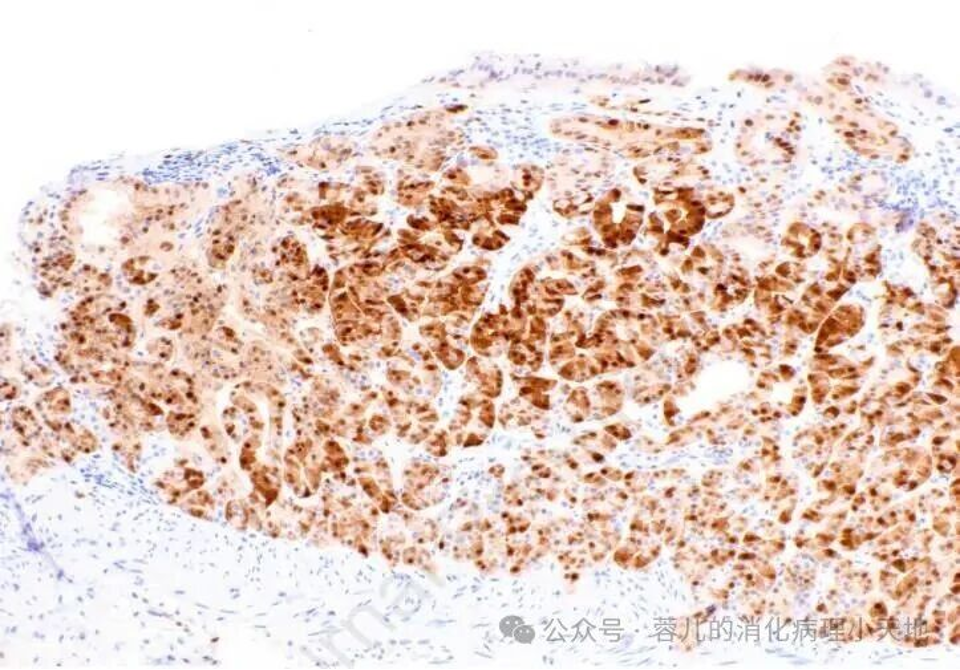

胃泌酸腺腺瘤由扩张且呈角状的腺体组成,这些腺体以主细胞分化为特征,其特征为嗜碱性胞质和均匀的圆形核

Cyclin D1 呈弥漫阳性染色